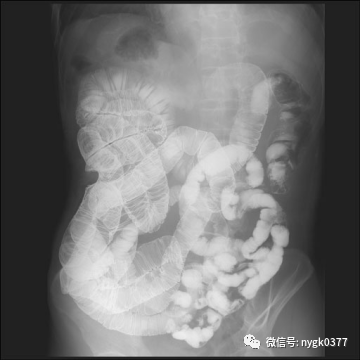

南阳市骨科医院(独山院区)

近期我院引进日本岛津 C200多功能影像中心系统,该设备拥有性能完善的影像链系统,保证了其以很低的剂量得到优质的图像。配置的高性能动态平板探测器系统,使其图像质量更加优越。模块化设计理念使其功能更加丰富,覆盖了骨科、消化科、儿科、妇科、泌尿、等多科室应用。床体多中心运动设计,使其能更好的完成泌尿造影、ERCP、输卵管造影等应用需求。突破性的功能设计延伸到骨密度检查、金属关节置换周边图像采集、DSA等图像采集需要。

02、消化系统检查功能

2、消化道特殊造影影